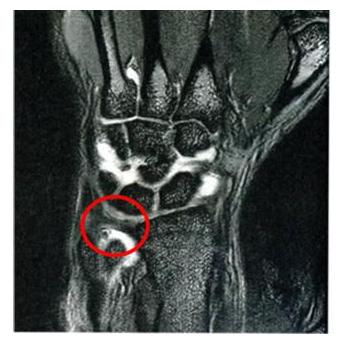

什么是腕三角软骨盘损伤?

并不是所有的手腕疼都是腱鞘炎,还可能是三角软骨盘损伤,这也是临床骨科最常见的疾病之一,在体操、篮球、排球运动员中最常见。

绝大多数的腕部三角纤维软骨盘损伤是慢性劳损所致,主要是因为运动中前臂和腕部反复的旋转负荷过度,软骨盘长期受到碾磨或牵扯,以及侧关节受力过度引起。

(2)急性的三角软骨盘损伤

急性的损伤大多是摔倒时手撑地引起的。此时,由于前臂极度旋转,腕三角软骨盘会被拉紧、扭动,如果旋旋力度过大,就会使软骨盘的附着处撕断或分离,甚至使软骨盘本身撕裂,远侧关节间亦发生不同程度的扭伤、分离或脱位。

腕三角软骨盘损伤的伤者,虽然没有腕部肿胀,但会感到手腕无力(有点握不住东西)、腕关节内部疼痛(这种疼痛在前臂或腕部做旋转时更明显,像用手撑桌面起身时)、旋转无力(特别是扭毛巾,转门把手时)。

简单总结一下:腱鞘炎发作多是因为腱鞘磨损,主要症状是手腕大拇指侧疼痛;而三角软骨盘损伤,发病部位在手腕处,主要表现为手腕小指侧疼痛,有无力感。